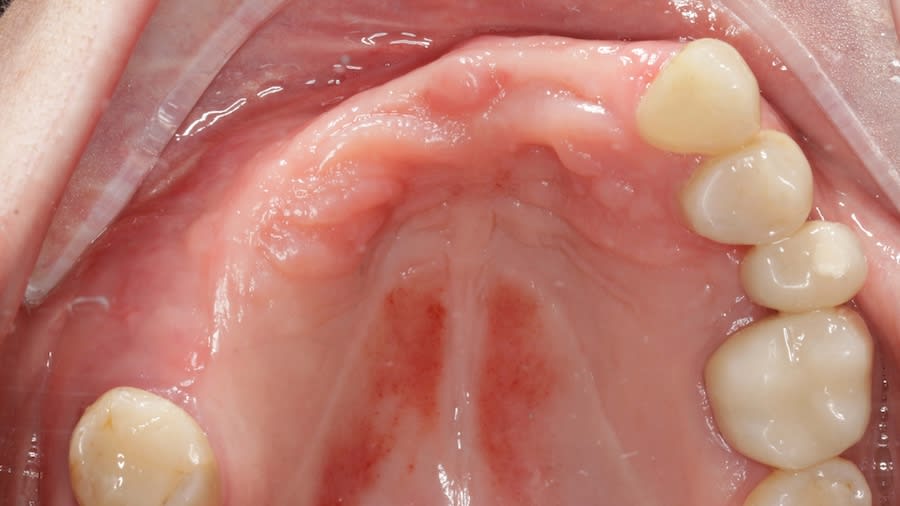

Case 1 (Figure 3 through Figure 24) depicts a 3-year follow-up of combined osseodensification sinus protocol IV in a severely resorbed maxillary ridge with ≤0.5 mm bone height in molar sites and horizontal deficiency at the first premolar site, using a two-stage approach for implant placement.

Case 2 (Figure 25 through Figure 36) illustrates a 3-year follow-up of the osseodensification sinus protocol IV in a severely resorbed right maxillary ridge with <0.5 mm bone height in molar sites, using a two-stage approach for implant placement.